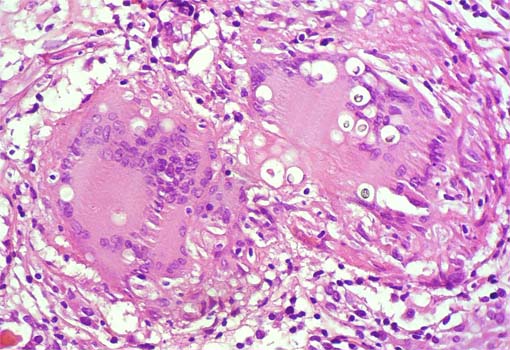

Figura 6.

H&E, X400.